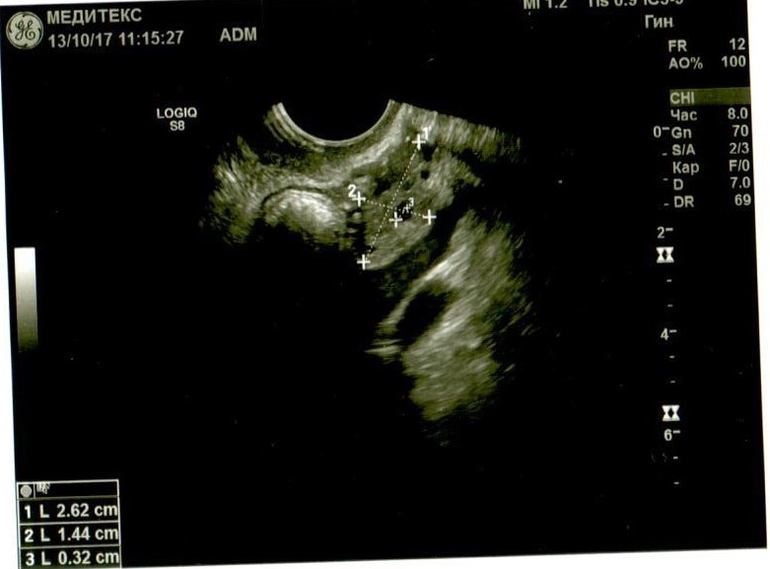

Если можно, посмотрите. Буду очень благодарна. Не очень в этом разбираюсь, поэтому выкладываю все снимки и заключение узистки.

Добрый день! У Вас в самой структуре яичника имеются гиперэхогенные включения, которые говорят о перенесенном воспалении, при этом о спайках может говорить только расположение яичников возле матки ( это если опираться на описание, так как на фото не видно). Однозначно, имеет место хронический оофорит. И в эндометрии мне не нравится зона в области дна. Врач ее даже выделила, но не описала. Эндометрий неоднородный, стоит сделать УЗИ на 5 день цикла повторно.